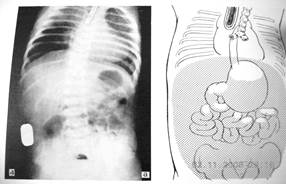

Рис.11. Атрезия пищевода с нижним трахеопищеводным свищем (боковая проекция)

Рис.12. Атрезия пищевода с нижним трахеопищеводным свищем (прямая проекция)